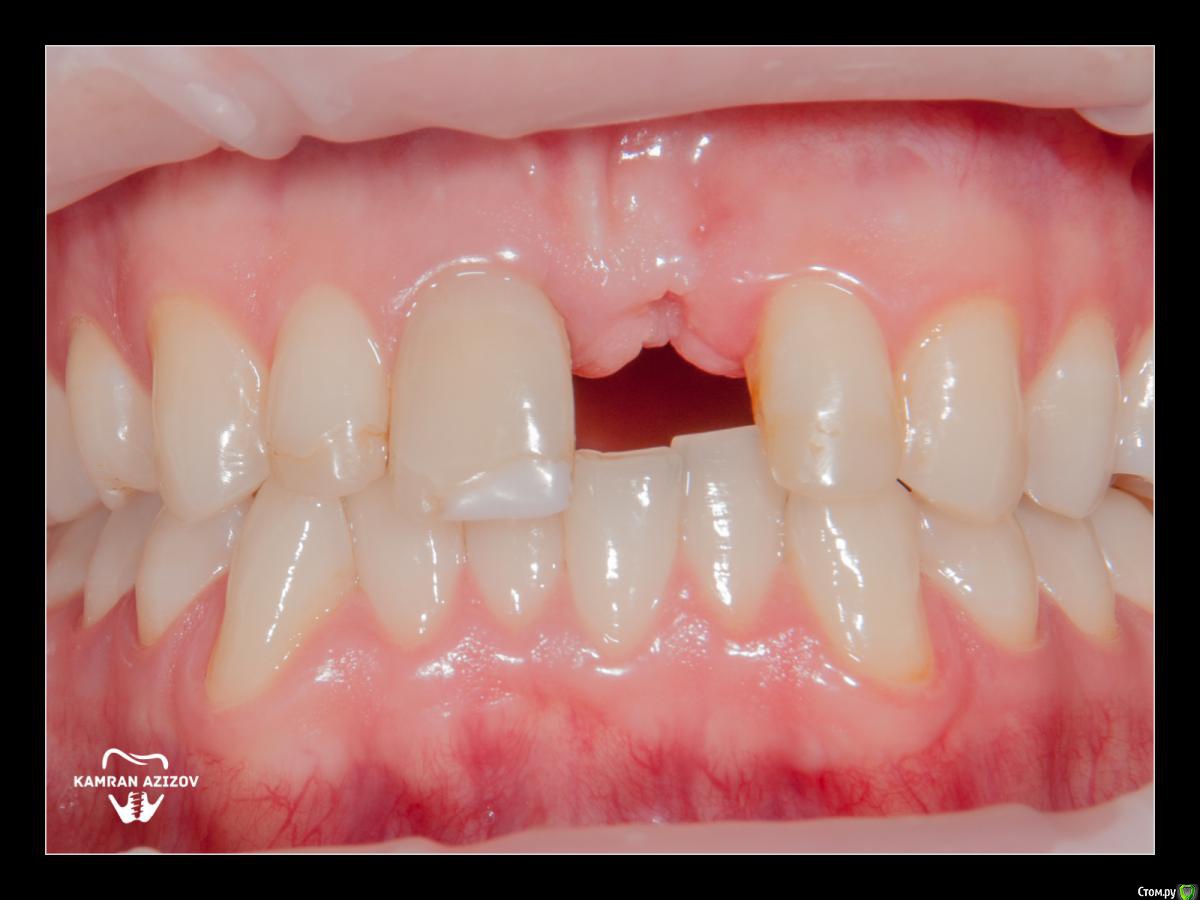

kamranchick Опубликовано 8 октября, 2019 Поделиться Опубликовано 8 октября, 2019 удаление зуба+консервация лунки с вестибулярным ССТчерез 2 месяца имплантация с фдм по карлоссучерез 4 месяца замена на более длинный фдм и широкийпостоянная коронка 5 Ссылка на комментарий

Irouil Опубликовано 9 октября, 2019 Поделиться Опубликовано 9 октября, 2019 Жаль фотки до удаления нет, кажется там дефект вестибулярно был Ссылка на комментарий